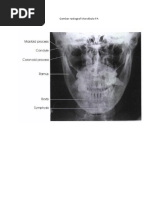

Radiographic Critique Form (RCF)

Examination = Mandibula PA Ya/Tidak Diskripsikan hasil analisis

Gambaran anatomi dalam radiograf? Ya Keseluruhanbagian mandibular termasuk ramus,

dan body mandibular

terproyeksidantidakterpotong.

Apakah gambaran anatomi tampak sesuai Ya Kedua condyles mandibular

dengan proyeksi ini? danangulusmadibulaterproyeksidenganjelas.